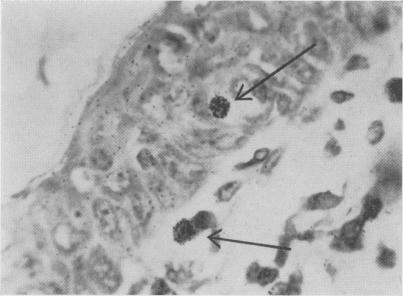

CELLULAR ASPECTS OF THE TUBERCULIN REACTION.

Postgrad Med J. 1964 Feb;40(460):66-9. doi: 10.1136/pgmj.40.460.66.